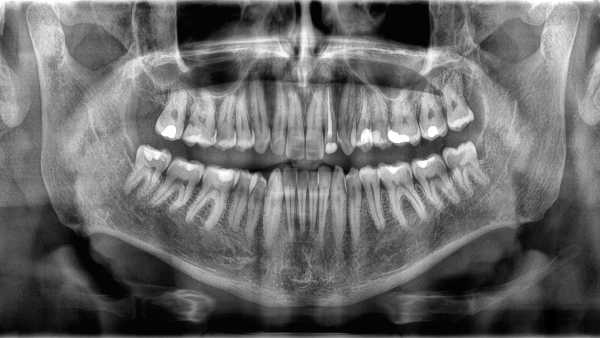

На перший погляд, зуби та кістки здаються схожими. То чому ж зуби не вважаються типом кісток? (Зображення: Carbonero Stock via Getty Images)